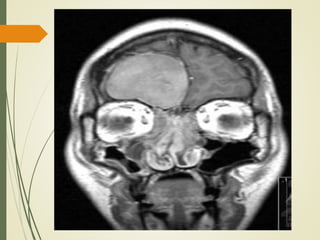

• #43 El diagnóstico se confirmó con tomografía computarizada que muestra una lesión de pared lisa llenar un seno ampliado, con áreas de hueso adelgazado o dehiscentes, por lo general entre el mucocele y la órbita o la fosa craneal anterior.

• #45 Resonancia Magnética en el mismo paciente.